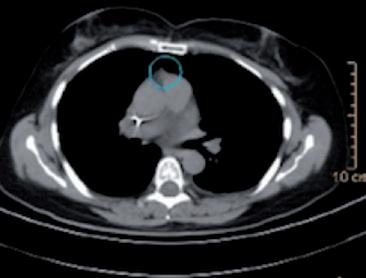

La stadiazione sistemica è stata effettuata mediante scintigrafia ossea e TC total body con mdc. La TC con mdc ha evidenziato la presenza di voluminosa eteroplasia mammaria di sinistra con aspetto multi nodulare plurifocale con estensione alla stazione linfonodale infraclaveare e ascellare di questo lato. Apparentemente conservato il piano di clivaggio rispetto alla parete toracica sottostante. Adenopatie interessanti le stazioni del mediastino superiore con diametro singolo sino a 4 cm ed estese bilateralmente lungo la linea mediana. Altre adenopatie in corrispondenza della stazione della carena tracheale e dell’ilo di sinistra. Alla cupola epatica destra evidente centimetrica nodulazione con enhancement marginale e verosimile componente necrotica centrale

sospetto per secondarismo. Centimetrica area di lisi verosimilmente secondaria del margine laterale sinistro al III medio dello sterno. Encefalo negativo. La scintigrafia ossea ha dimostrato un discreto iperaccumulo del tracciante osteotropo al margine sinistro del corpo sternale, dubbio per possibile infiltrazione di nota malattia.

Alla RMN encefalo con mdc di approfondimento venivano evidenziate plurime lesioni ripetitive (almeno 10)

in sede sovratentoriale (diametro massimo 10x12 mm in sede temporale destra) circondate da alone di edema. Ulteriore lesione sospetta in sede sottotentoriale vermiana paramediana destra (2,5x2,5 mm circa) (figura 1a e 1b).

Figura 1a e 1b. Evoluzione della neoplasia mammaria primitiva dalla diagnosi in aprile 2023 alla risposta dopo 7 cicli di T-DXd in aprile 2024.